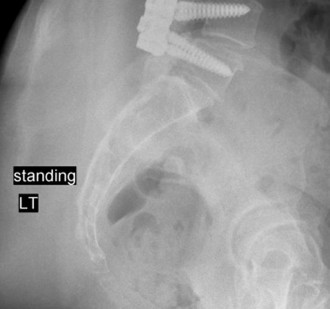

The final, critical step is rod contouring and reduction. To prevent future Adjacent Segment Degeneration, the titanium rods must be contoured to match the patient's ideal pelvic incidence and lumbar lordosis. The rods are seated into the proximal screws. Using reduction towers and careful cantilever forces, the rods are seated into the distal screws. This maneuver actively corrects the 25-degree kyphotic deformity, restoring normal sagittal alignment. The construct is cross-linked if necessary, and a robust posterolateral decortication and bone grafting (using local autograft from the laminectomy and allograft) is performed to ensure a solid arthrodesis.

Radiographic follow-up includes upright AP and lateral plain films before discharge to verify the maintenance of sagittal alignment and hardware integrity. The patient is discharged home or to acute inpatient rehabilitation depending on their functional mobility.

Long-term follow-up at 6 weeks, 3 months, 6 months, and 1 year will focus on assessing fusion mass consolidation and monitoring for any signs of hardware failure. More importantly, long-term surveillance (2 to 5 years post-op) will focus on the adjacent segments. By having meticulously restored the sagittal vertical axis (SVA) and regional lordosis during the index procedure, we have minimized the abnormal shear and compressive forces on the T10-T11 and L3-L4 discs, drastically reducing the patient's risk of developing Adjacent Segment Degeneration requiring revision surgery.